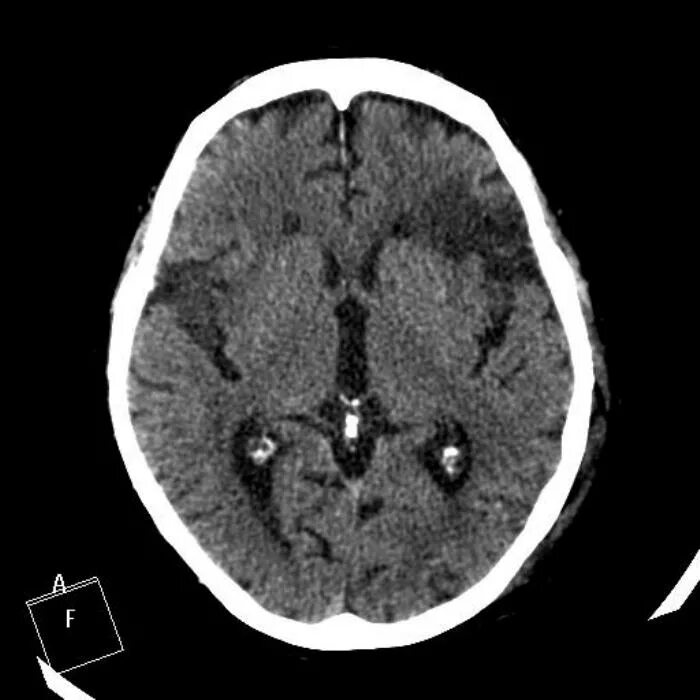

Онмк в бассейне сма